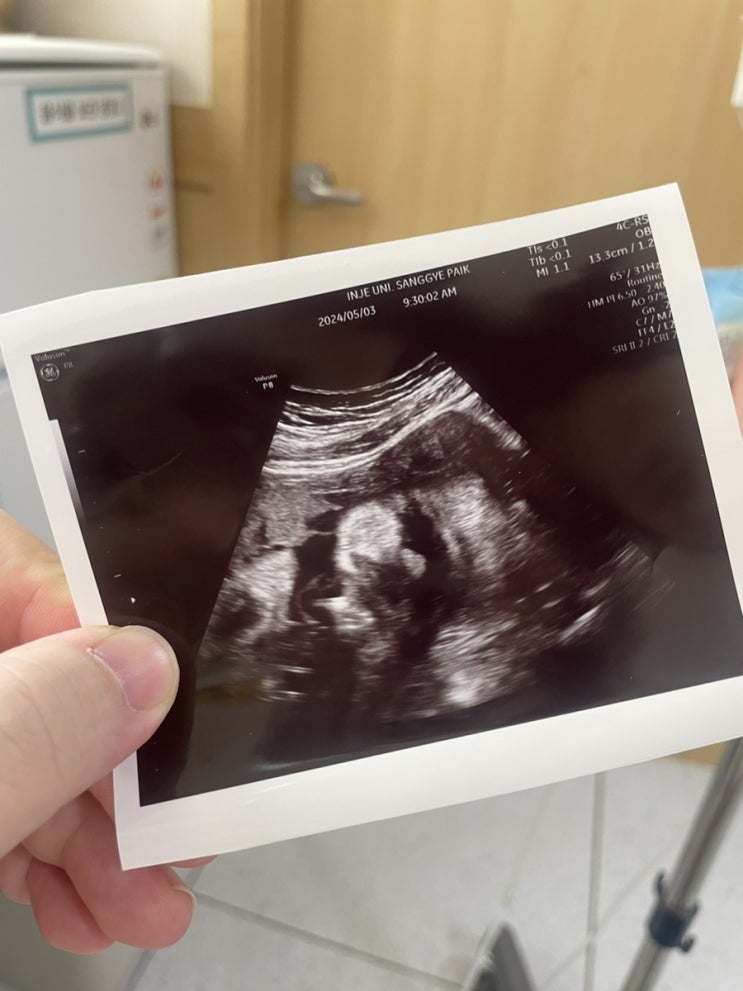

37w5d - 유도분만 시도 후 응급제왕으로 출산완료!!! 방울이 탄생❤️

매주 수요일에 외래를 가게되는데 37주도 마찬가지로 방문해서 다음주쯤 출산하고 싶다고 말씀드렸는데 안...